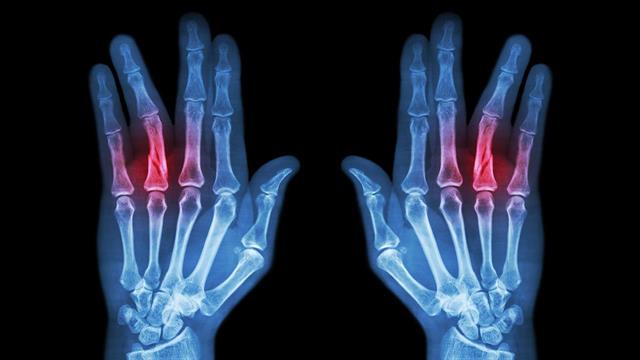

Σύμφωνα με τους αγγειοχειρουργούς «οι αγγειούμενοι μισχωτοί κρημνοί (μοσχεύματα) είναι ιστοί (δέρμα-λίπος-μύες ή και οστό) που μεταφέρονται μαζί με το αγγείο τους από μια υγιή περιοχή ενός μέλους σε μια άλλη πάσχουσα ή ελλειμματική σε απόσταση μέχρι και 40 cm».

«Η ανάγκη χρήσης αυτών των μοσχευμάτων σε χέρια ή πόδια προκύπτει όταν κάποια τμήματα αυτών των μελών έχουν χαθεί από τραύμα ή έχουν αφαιρεθεί χειρουργικά μετά από κατάκλιση, γάγγραινα (πχ διαβητικό πόδι) ή κακοήθη νεοπλασία και πρέπει το εναπομείναν οστό ή τμήμα να καλυφθεί με αυτούς, προκειμένου να αποφευχθεί ο ακρωτηριασμός», εξηγεί ο κ. Ιγνατιάδης.